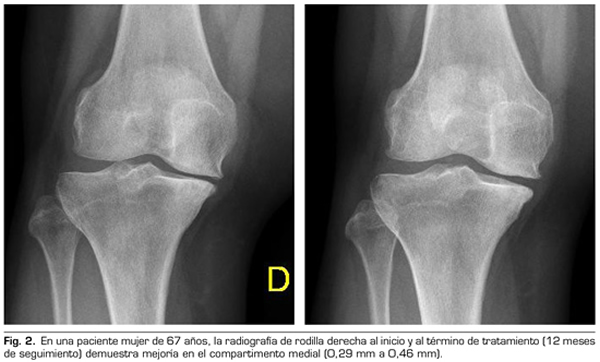

Variables radiológicas: en 53 pacientes analizados radiológicamente (según protocolo estandarizado) al año de seguimiento después del tratamiento con ozono, el compartimento interno aumento significativamente de 4.12 ± 1.41 mm a 4.4 ± 1.35 mm (p = 0.0008) y el compartimento externo aumentó de 6 ± 1.37 a 6.16 ± 1.4 mm (p = 0.0753).

Radiological variables: In 53 patients analyzed radiologically (according to standardized protocol) at one year of follow-up after ozone treatment, the internal compartment increased significantly from 4.12 ± 1.41 mm to 4.4 ± 1.35 mm (p = 0.0008) and the external compartment increased from 6 ± 1.37 to 6.16 ± 1.4 mm (p = 0.0753).